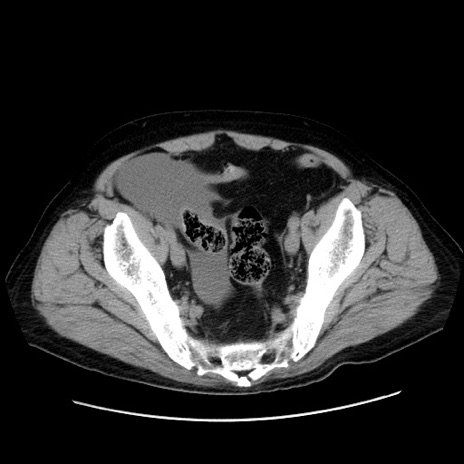

症例30(横断像)

【症例】80歳代男性

【主訴】臍周囲痛

【現病歴】約6時間前から臍下部痛が出現。次第に腹部膨隆・背部痛も生じてきたため来院。背部痛の場所は変化しない。

【身体所見】意識清明、BT 36.3℃、BP  131/87mmHg、P 87bpm、SpO2 100%(RA)、臍周囲自発痛・圧痛あり、反跳痛なし、自発痛部位に一致して板状硬あり、腹部膨隆、腸雑音減弱、CVA tenderness両側陰性。